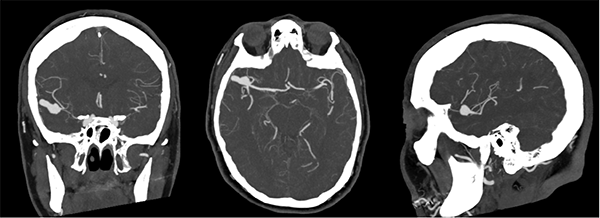

El laboratorio se encontraba dentro de parámetros normales, se realizó resonancia magnética (RM) de cerebro sin contraste, la cual mostró una imagen hipointensa en secuencia GRE a nivel del surco silviano derecho y adyacente a la misma se observa edema perilesional que se extiende al lóbulo temporal (Figura 1). Se realizó angiotomografìa para descartar una malformación vascular subyacente, en la cual se advirtió una dilatación aneurismática polilobulada de 20 x 6 x 9 milímetros (Figura 2).

Figura 1: A nivel del surco silvano derecho y en relación a la arteria cerebral media homolateral, se evidencian imágenes de baja señal en secuencia de gradiente eco (GRE) de aspecto sacular (A), en secuencia FLAIR se observa a nivel del surco Silviano en territorio de la arteria cerebral media derecha imagen hipointensa de forma sacular sugestiva de probable formación aneurismática, adyacente a la misma se aprecia hiperintensidad en parénquima cerebral sugestiva de edema (B y C).

Figura 2: Se observa en Angiotomografía de vasos intracraneanos en sus tres cortes anatómicos a nivel de la bifurcación de la arteria cerebral media derecha una dilatación aneurismática sacular, irregular y polilobulada sin evidencia de signos de trombosis o aterosclerosis.